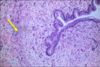

Renal circulation

- Interlobular artery at the bottom center

- Intralobular arteries that branch from it.

- Afferent arterioles can be seen branching to the right at the top of the field

- Round, dark red-staining glomeruli

- Peritubular capillary plexus is demonstrated at the upper and lower right-hand corners of this slide